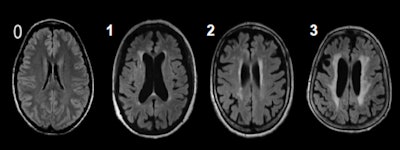

The investigators sought to determine the frequency and associated risk factors for white-matter lesions in a population cohort and potentially discover a connection with heart failure. They used the Fazekas score for the classification of the white-matter lesions, and raters were blinded to other medical information of study participants. History of heart failure and other diseases were ascertained as part of the self-reported medical history questionnaire.

The odds ratio for heart failure was 2.5 (95% confidence interval: 1.1; 5.6) and numerically higher than the odds ratio for stroke (odds ratio: 2.0; 95% confidence interval: 1.0; 3.8). Additionally, analysis of the duration of heart failure indicated that a long-standing diagnosis of heart failure is associated with increase of white-matter lesions (odds ratio: 1.3 for heart failure duration < 3 years; odds ratio: 1.7 for heart failure 4-6 years duration; and odds ratio: 2.9 for heart failure diagnosis > 6 years).